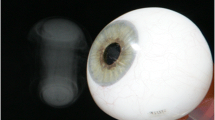

Our laboratory has recently developed a method to deliver medications to the surface of the eye via aerosols which are formed into discrete doses utilizing toroidal vortices (e.g., “smoke rings”) that enabled accurate and controllable delivery of small administered volumes [16]. Because this method of delivery is significantly different from other aerosol or small volume approaches tested previously, we investigated here several different analytical techniques for the characterization of this aerosol delivery system. This delivery technology produces micron-sized droplets containing dissolved drug, moving at variable velocities. Therefore, advanced analytical methods needed to be adopted to characterize this dynamic system, and these methods may prove to be useful in analyzing other aerosol systems such as nasal sprays and inhalation aerosols as well.

The objective of this study was to characterize the clinically relevant physical performance features of this delivery device, namely characterize droplet size dynamics during vortex delivery, the bulk vortex and individual droplet velocities, as well as the impaction force of the toroid onto a surface in order to determine if the device likely performs in a safe comfortable and reliable manner suitable for future clinical investigations.

When designing an ophthalmic drug delivery device, several key features need to be investigated in order to ensure patient safety, tolerability, reproducibility, feasibility, and ultimately, efficacy. The features of this device that have been identified to play a major role in the performance and feasibility of the device are related to the nature of the generated toroidal vortices and how a patient may experience them. The main features we investigate here are the components that can contribute to the patient comfort and usability. The components that contribute to the comfort of administration are all related to the nature of the impact of the droplets onto the eye and the velocity and size of droplets. In addition, these parameters also influence the performance because there exists a balance between velocity and PSD for optimal deposition because inertial deposition is governed by the mass and velocity of the individual droplets. Furthermore, the feasibility of the device pertains mostly in the ability to deliver the medicine before an instigated blink reflex can block or disrupt the dose [18]. For this, the bulk velocity over a distance was mapped to determine if the velocity of the vortex is adequate to escape a possible blink reflex.

Another critical aspect of the device is the ability to deliver the aerosol at an effective, safe, and comfortable speed. A high-level balance between droplet velocity and impaction force is required here, because the aerosol needs to be moving fast enough to impart adequate inertial characteristics onto the droplets so they can be deposited effectively on the eye surface without being intercepted by a possible blink reflex, while still being gentle enough to not cause discomfort.

Previously, Müller et al. showed that when comparing an eye drop to an eye spray, there was an inverse relationship between the distance of application and the force for the spray and a direct relationship between impact force for drops and distance. In essence, the drops gain momentum and impact harder the further they are away, while the spray loses velocity the further away it is administered. While this decrease in impact force from a distance is preferable, a drawback with spray type devices is that they emit aerosol in a cone-type geometry, meaning that the farther the device, the larger the diameter of the cone. Müller et al. found that at just a distance of 1 cm, the diameter of the cone was ~ 25 mm, and not only is this larger than the diameter of the exposed portion of the eye, this distance corresponds to an impact force of about 10 mN. This impact force corresponds to about a 1-g-force, nearly 2000 times the forces generated from the toroids found in our studies and triple the force created by an eye drop at the same distance. At an equivocal distance of 3 cm, the spray force from a spray is reduced ~ 5 mN, but at the cost of increasing the diameter of the spray cone to about 35 mm, where a large portion of the spray is likely to miss the ocular surface. Furthermore, because the velocity and impaction forces of these toroidal vortices are so low relative to sprays or even eye drops, it very unlikely that there will be any disruption of the corneal surface or cause any discomfort for a patient.

In summary, we found that despite the large differences in both bulk and maximal droplet velocity, the resulting impact forces generated from these toroidal vortices change very little, which is likely due to the small mass contained in each vortex. Furthermore, it was determined that this impact force is far below the threshold for what a patient could tolerate relative to other forces currently used clinically in patients. In addition, we also measured the size of the droplets to be on the order of which would be suitable and comfortable for ocular drug delivery and that the delivery of the toroid would likely outpace reflex blinking if it were to be triggered by the device. These preliminary studies have offered support for advancing the investigation into a preclinical setting and much more testing would need to be conducted to show the performance, safety, and efficacy of the delivery device in animal and human subjects.